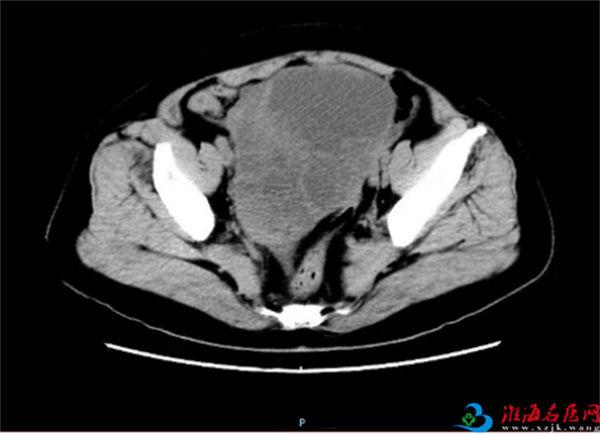

为进一步明确瘤子性质以及和周围组织关系,朱彦玲给王老太安排了腹部增强CT检查:子宫切除术后,盆腔巨大囊实性肿物,最大横截面积19*12cm,考虑右侧卵巢来源,浆液性囊腺癌可能。